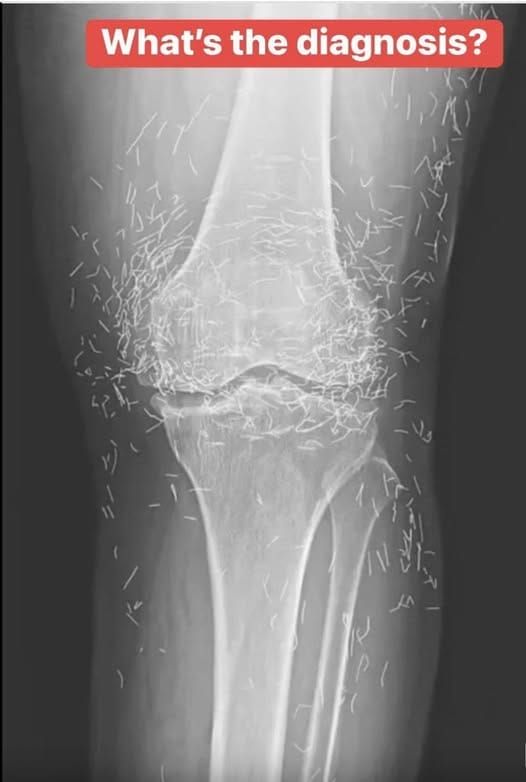

A 65-year-old woman came to the clinic after experiencing months of chronic knee pain

Years later, when doctors took X-rays to evaluate her knee condition, they weren’t prepared for what appeared on the images. Her knees were filled with dozens of bright, metallic flecks — tiny needles embedded deep within the joint area.

The findings were later documented in a case published by the New England Journal of Medicine.

While striking, the discovery raised immediate concerns.

Beyond inflammation, the needles created another problem: imaging complications. Metal objects can obscure parts of the anatomy on X-rays, making it harder for doctors to clearly assess joint damage or disease progression.

Even more concerning, the presence of metal inside the body can make certain scans dangerous. MRI machines rely on powerful magnetic fields, and embedded needles may shift during scanning, potentially damaging blood vessels or surrounding tissue. In short, future diagnostic options for this patient became limited.